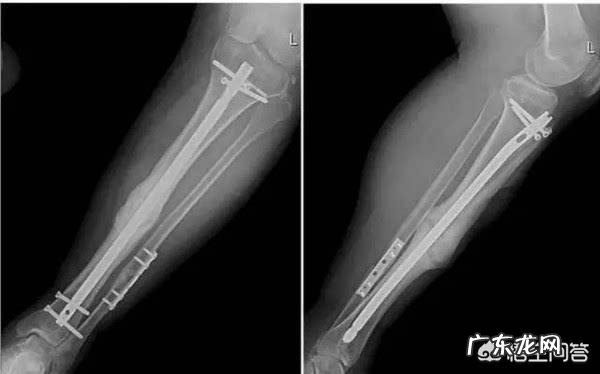

胫腓骨双骨折髓内钉手术后3个月可以走路了吗?胫腓骨双折术后引流管拔除以后即可以开始康复锻炼了,不知道您具体的伤情,没有片子可以分析,但是已经三个月了,是您赶紧开始康复锻炼的时候了 。

那么按照正常的骨折术后的康复规律,术后三个月应该已经可以单拐或者脱拐步行了 。

当然因为您的具体骨折情况我们看不到,也没看到您骨折术后的片子 。腓骨下段的骨折由于其先天的血供缺点骨折愈合略慢,患者脱拐的时间可以适当延长,但是下地步行的时间不宜拖得过晚 。